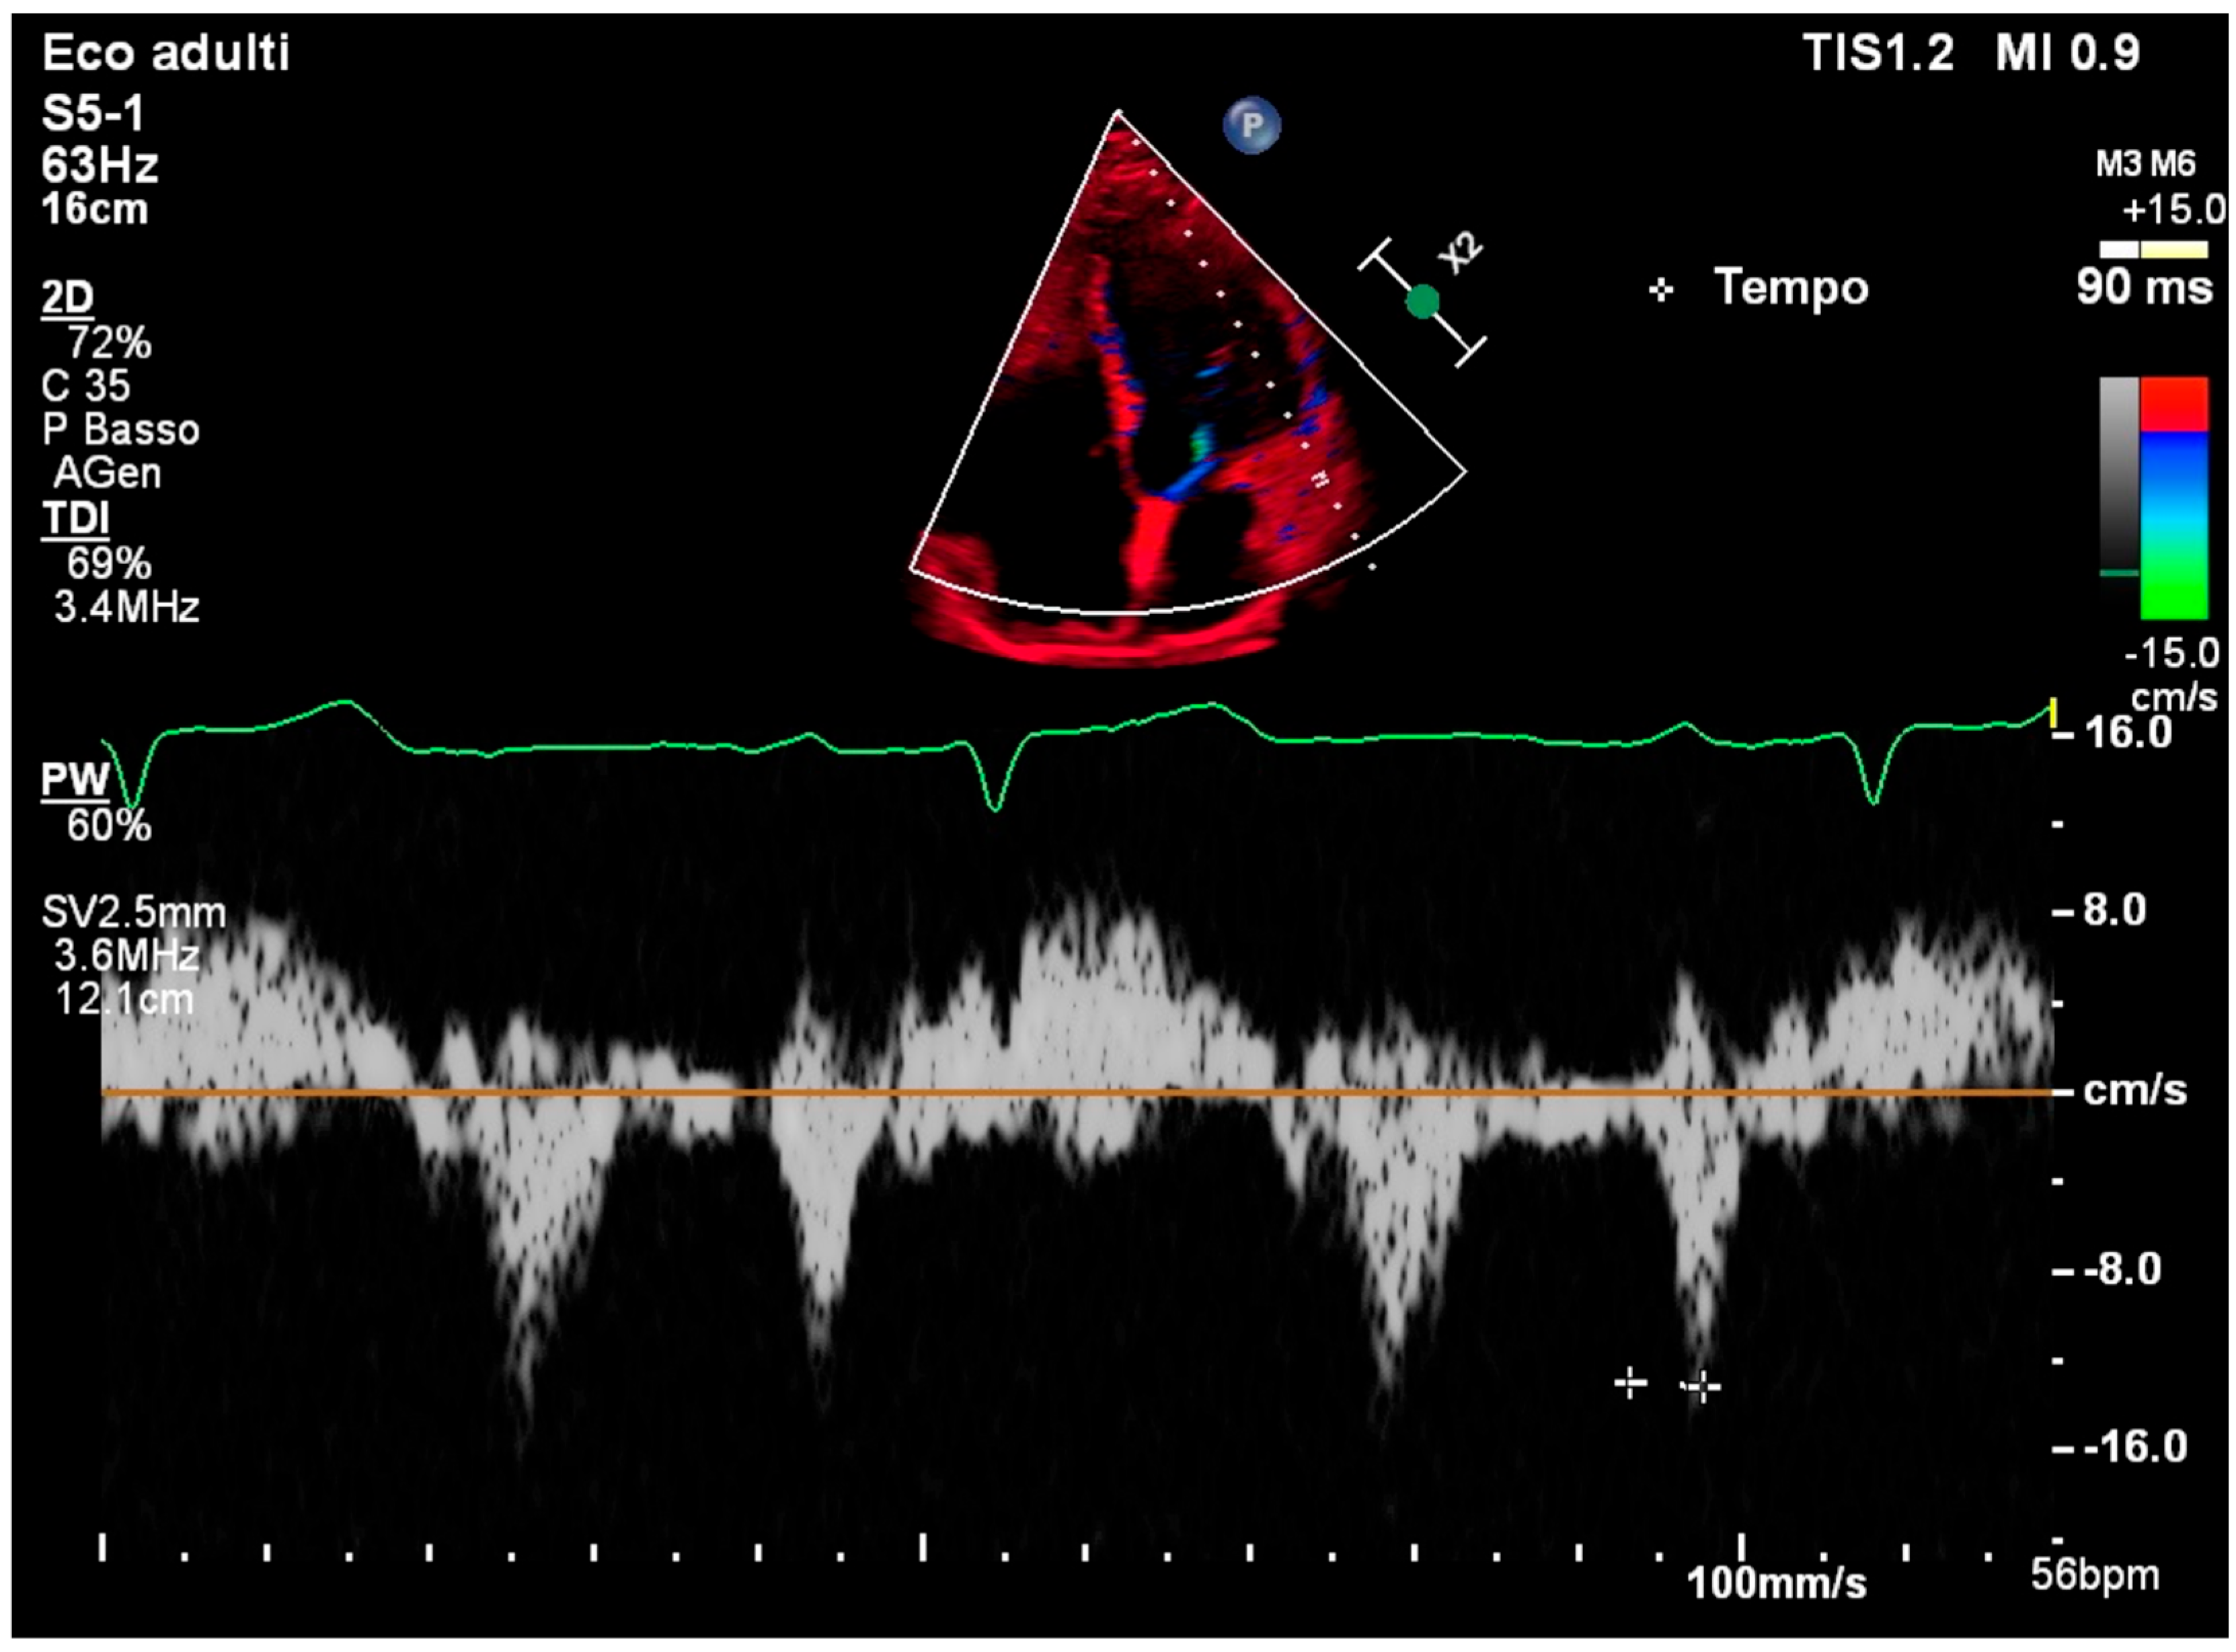

2. Case Presentation